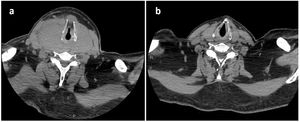

The day after the last consultation, the patient returned to the emergency department due to clinical worsening, with dyspnoea at rest. An urgent neck CT scan revealed compression of the airway at the level of the hypopharynx, due to the large goitre already described by ultrasound, which extended from the hypopharynx to the plane of the sternoclavicular joint (Fig. 1a). The patient required orotracheal intubation (which required exeresis of the thyroid isthmus) and admission to the ICU.

Given the marked clinical improvement, and despite not having a definitive diagnosis, one and a half months after admission, the patient was discharged from hospital with oral corticosteroid therapy, pending possible thyroidectomy. One month after discharge, the control CT scan found a significant reduction in mass size (RTL 23cc [2.8×2.1×7.5cm] and LTL 21cc [2.9×1.7×6.6cm]) (Fig. 1b), and laboratory tests revealed elevated serum IgG4 (307mg/dl), which accounted for more than 40% of total IgG. For this reason, an immunohistological review of the isthmectomy specimen was requested by pathology, which showed >60 IgG4+ cells/high power field.